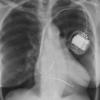

Ao nipple

Date: 01/07/2012

Views: 3014

(left superior intercostal vein)

Views: 3024